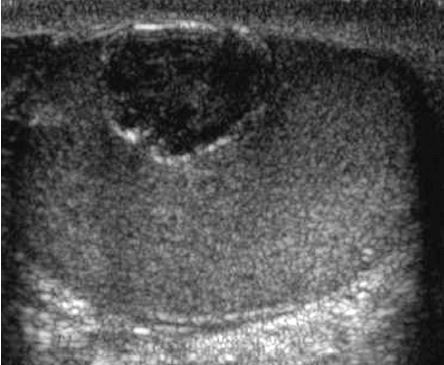

Tubular Ectasia of the Rete Testes

• The rete testes are a complex collection of small tubules that are located in the mediastinum of the testis. Fluid from the seminiferous tubules drains into the rete testis and then exits the rete testis via the efferent ductules. The efferent ductules then converge into the head of the

epididymis.

• Tubular ectasia of the rete testes is believed to be caused by some degree of outflow obstruction of the seminiferous fluid. Perhaps this is the reason why it is frequently associated with testicular cysts and spermatoceles of the epididymal head. It is also more commonly seen in patients with a history of inguinal surgery, such as hernia repairs and vasectomies.

• The key to making the diagnosis and distinguishing tubular ectasia of the rete testes from cystic testicular tumors is to note the bilateral involvement when present and to recognize the elongated shape on long-axis views of the testis.